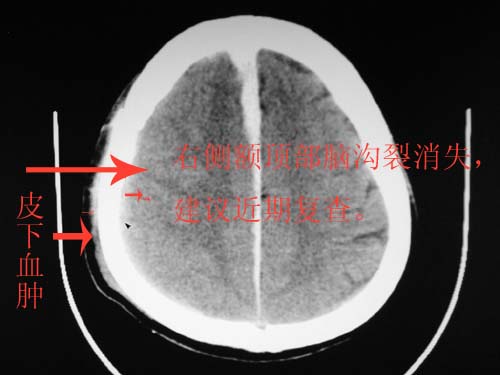

这个病人年龄不小吧,右侧脑沟不清,中线结构稍有左移,右侧额颞顶及右镰旁硬膜下血肿,另有蛛血,骨折。